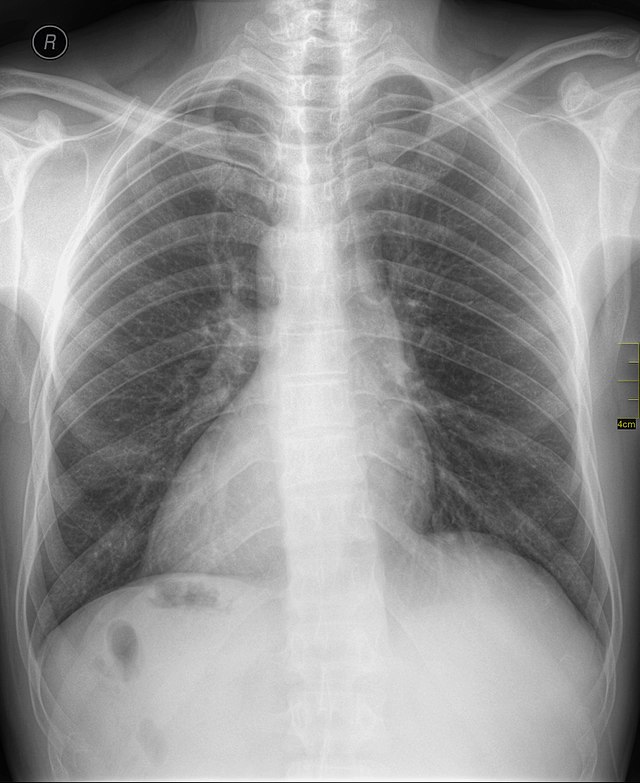

Example 3

Diagnosis

Cannonball metastases